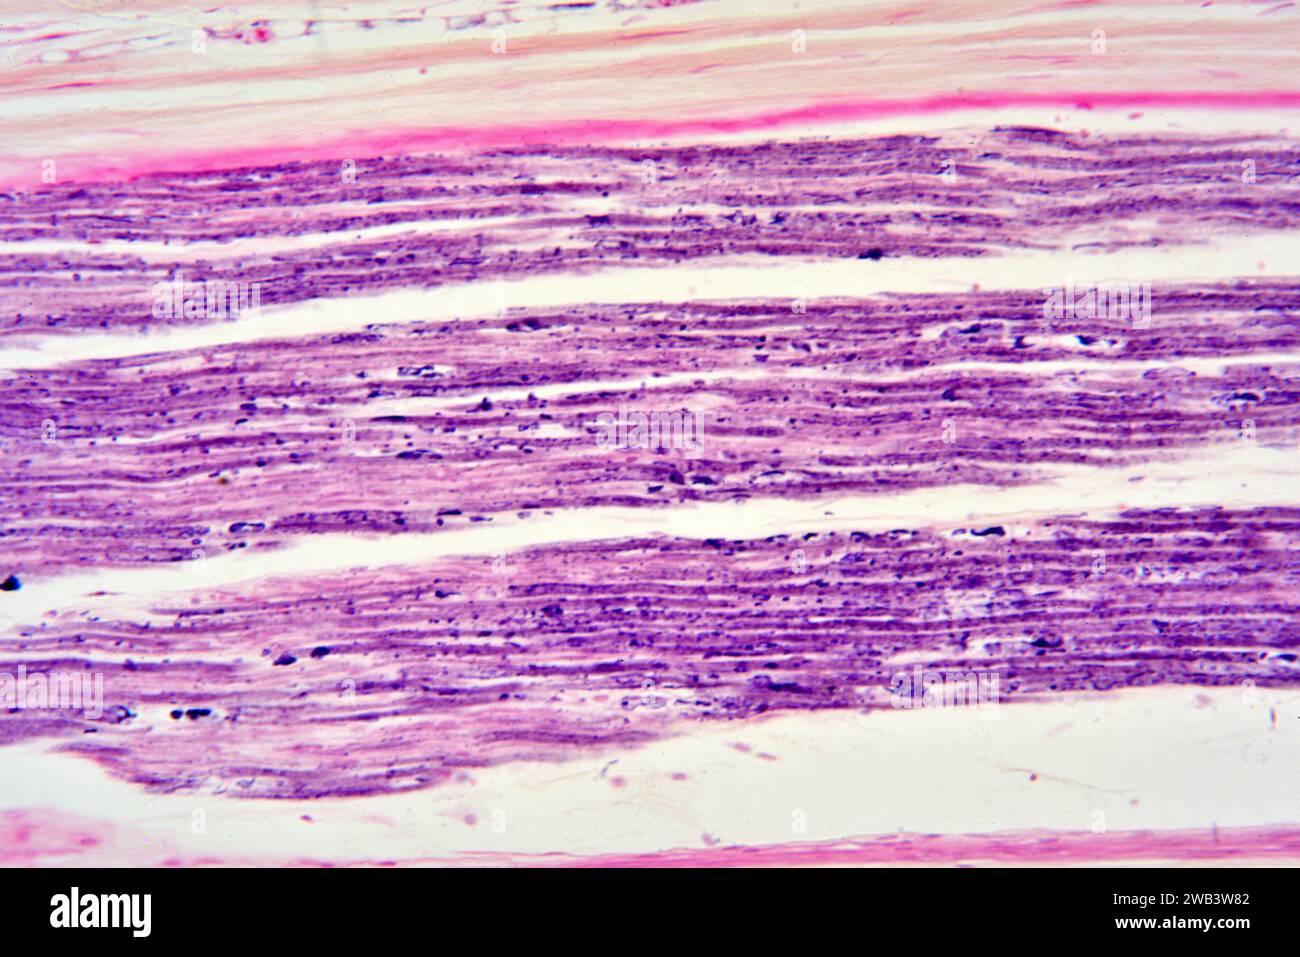

Nerf sciatique humain ou nerf ischiadique. X125 à 10 cm de large. Banque D'Imageshttps://www.alamyimages.fr/image-license-details/?v=1https://www.alamyimages.fr/nerf-sciatique-humain-ou-nerf-ischiadique-x125-a-10-cm-de-large-image591999410.html

Nerf sciatique humain ou nerf ischiadique. X125 à 10 cm de large. Banque D'Imageshttps://www.alamyimages.fr/image-license-details/?v=1https://www.alamyimages.fr/nerf-sciatique-humain-ou-nerf-ischiadique-x125-a-10-cm-de-large-image591999410.htmlRF2WB3W82–Nerf sciatique humain ou nerf ischiadique. X125 à 10 cm de large.